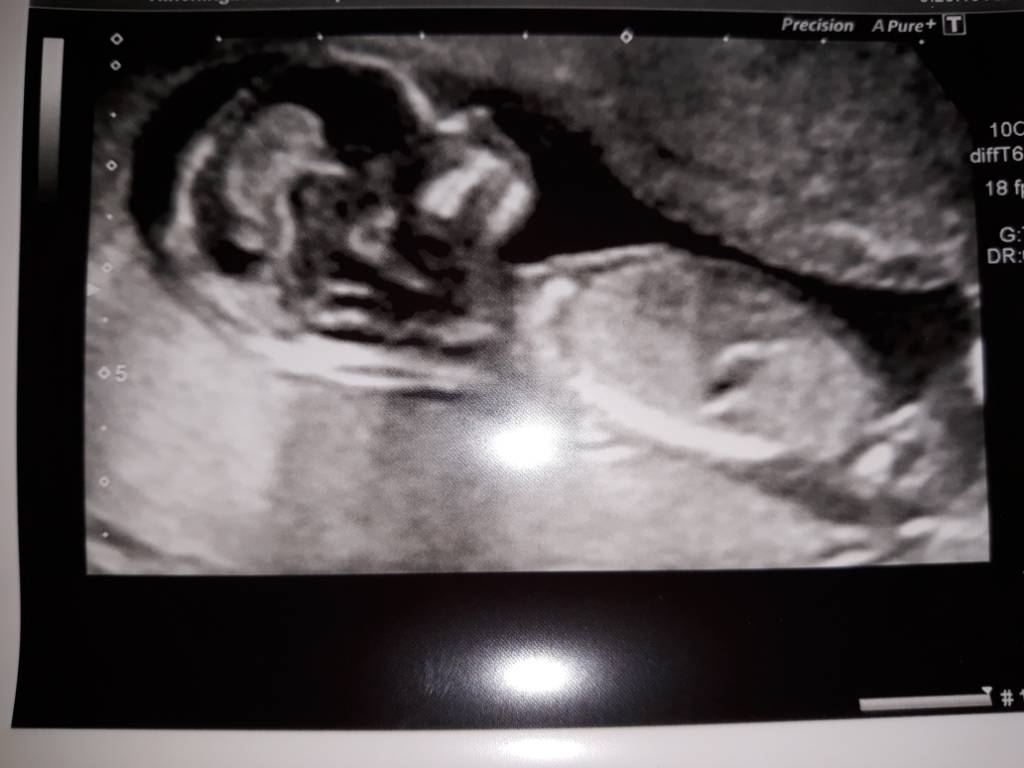

Tak wiec wizyta z 29.09 - gdy mój bobasek miał 13 t 2d.

Ktos dopatrzył sie ze ssie kciuk![]()